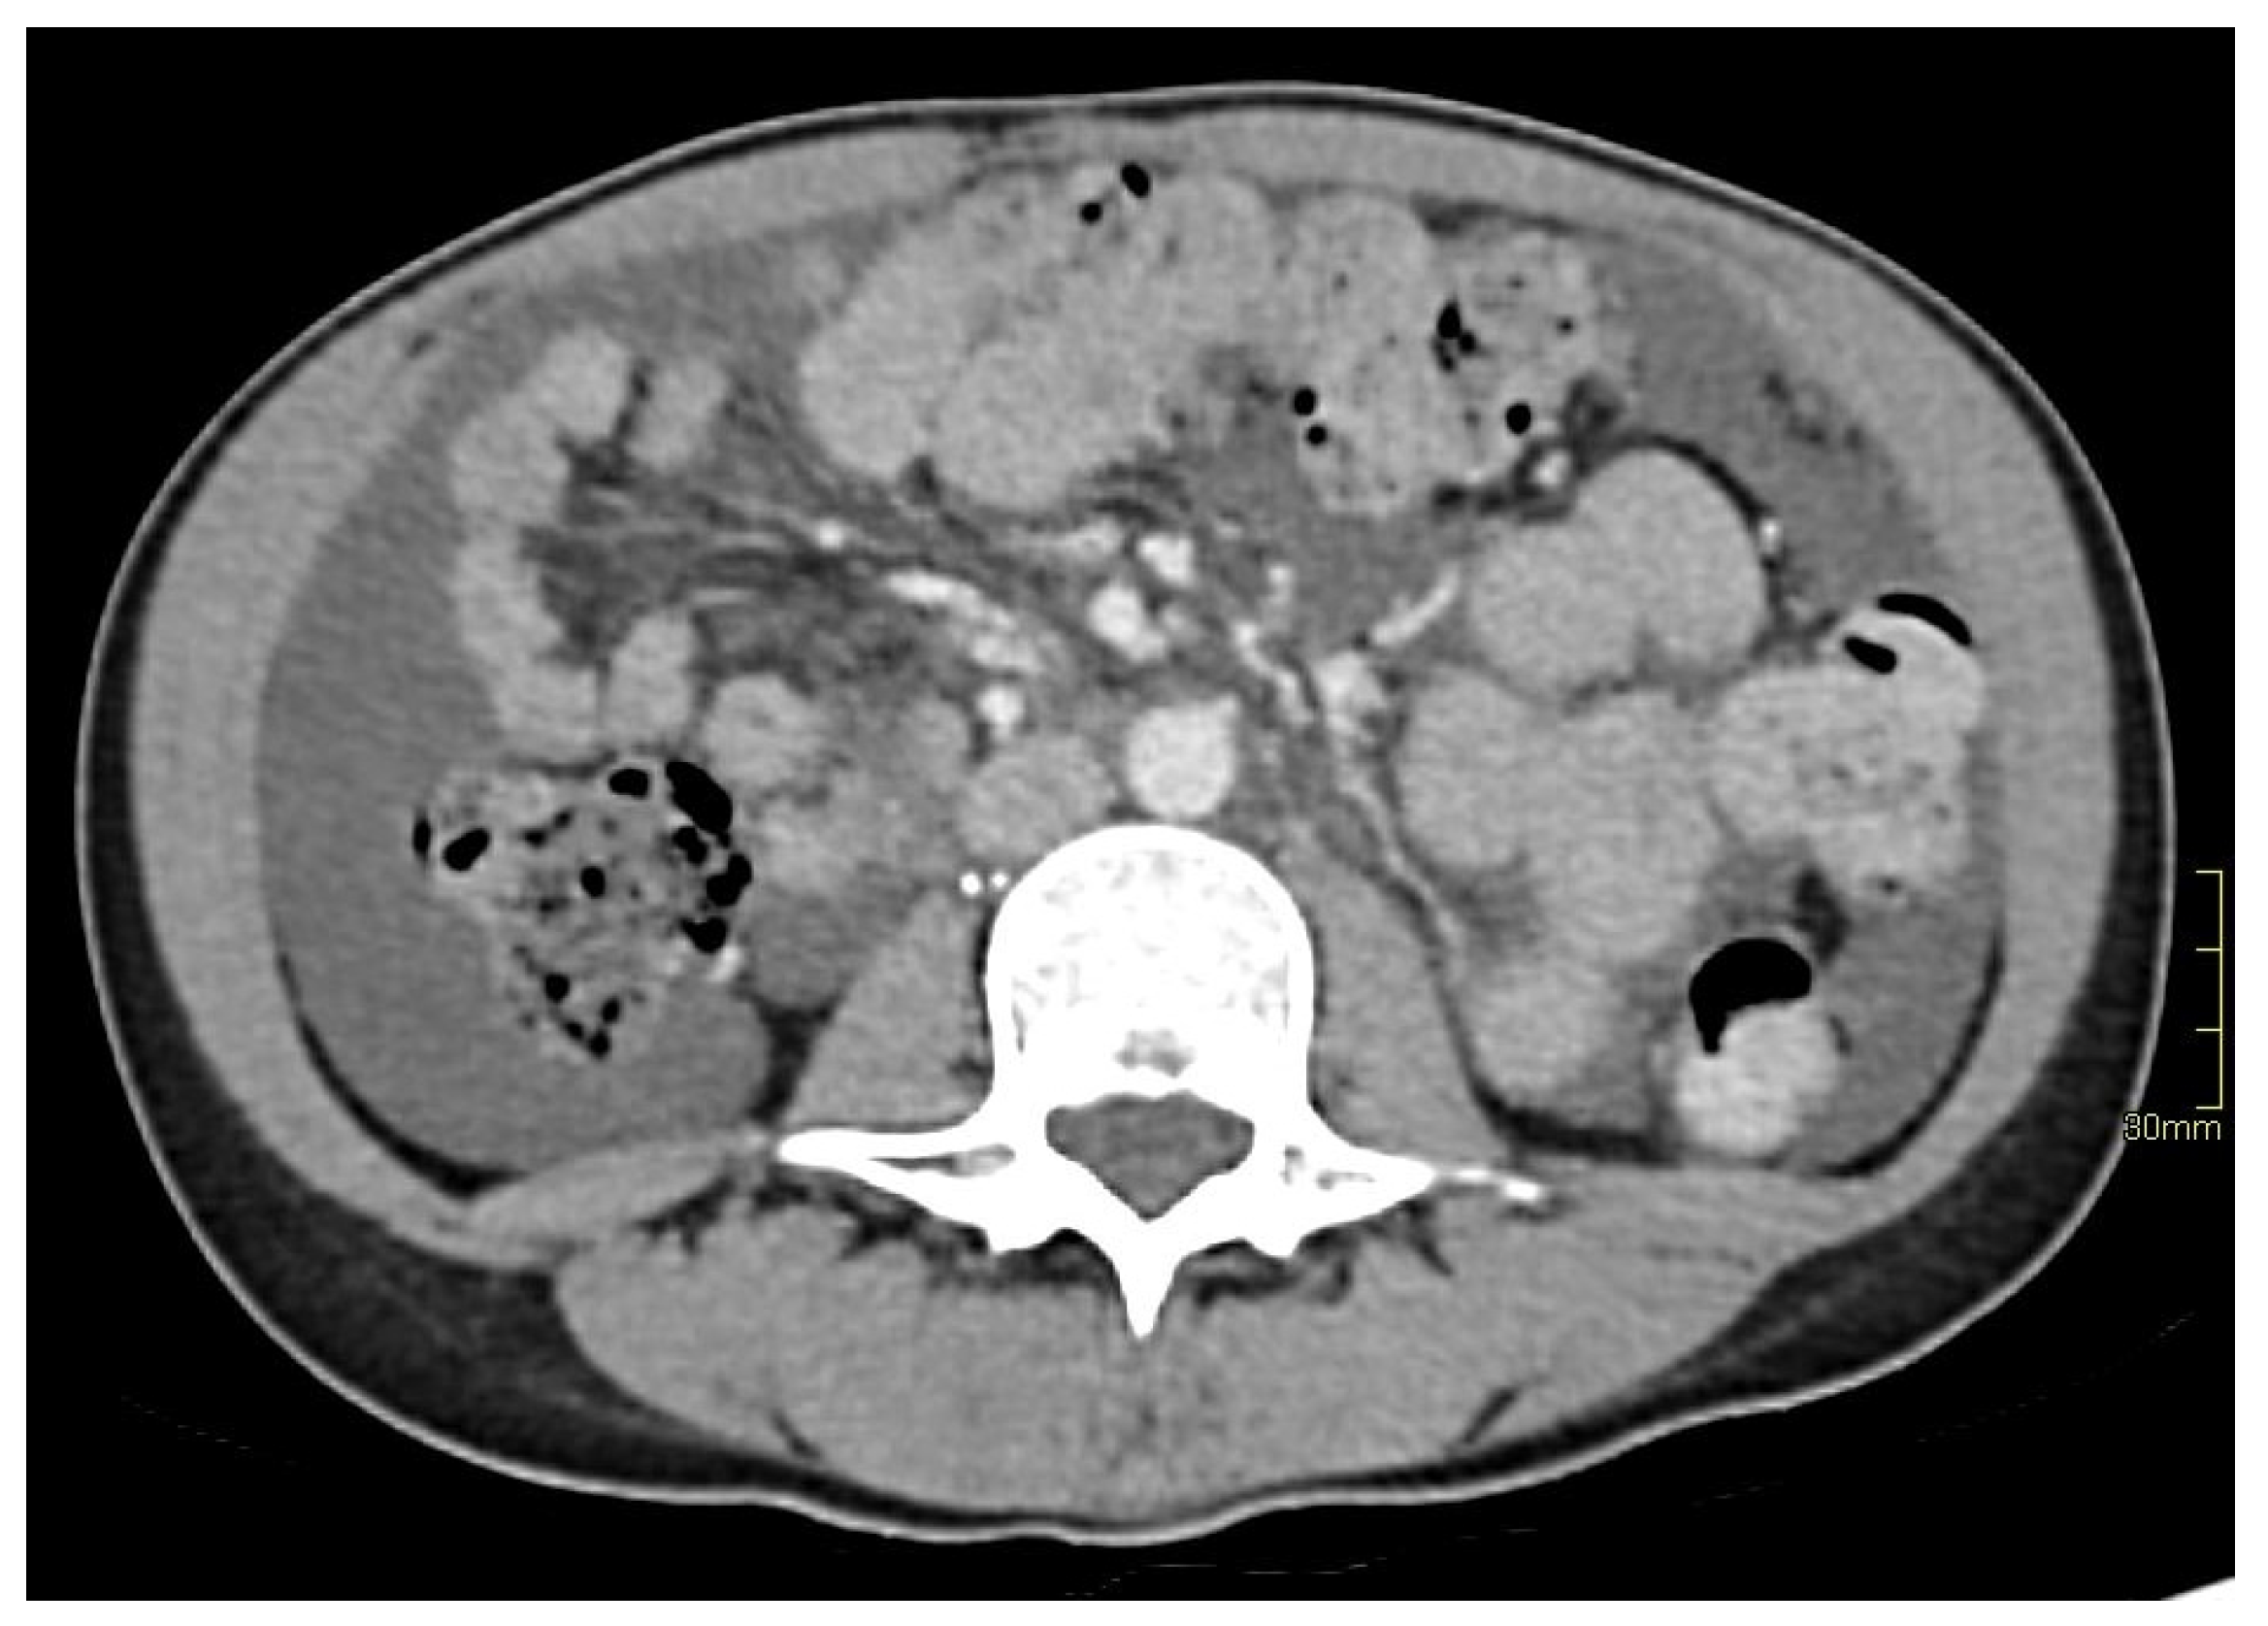

2. Case Report